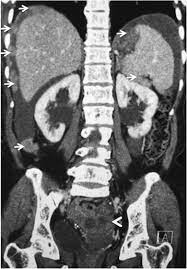

They show the different appearances of acc lung mets. Other names for this test: What is a ct scan with contrast? If not spread, you could conceivably see obstruction or changes in the bowel wall but it would likely be a big tumor nonetheless. I was then directed to lay down on the table.

Abdominal And Pelvic Ct from www.radiologyinfo.org The computer puts them together to make a 3 dimensional (3d) image. Early colorectal cancer can be subtle on ct scans showing only mild wall thickening, small polyps, or subtle lymph nodes in atypical draining location. Nothing found on us scan but fatty liver. I had my half way scan today so i'm now on. This shows the cancer more clearly. Acc has a tendency to spread to the lungs among other organs. Lab tests used to diagnose kidney cancer include: They show the different appearances of acc lung mets.

Effect Of Contrast Enhancement In Delineating Gtv And Constructing Igtv Of Thoracic Oesophageal Cancer Based On 4d Ct Scans Radiotherapy And Oncology from els-jbs-prod-cdn.jbs.elsevierhealth.com You may need to have a ct with contrast. Early colorectal cancer can be subtle on ct scans showing only mild wall thickening, small polyps, or subtle lymph nodes in atypical draining location. Identifying these lesions on ct scan performed for nonspecific symptoms can help identify interval crc and improve patient outcome. Ct scans can produce false negatives and false positives. A ct scan can help doctors find cancer and show things like a tumor's shape and size. Most pictures are taken from a ct scan where a contrast agent was used. Imaging tests usually can't tell if a change has been caused by cancer. If you mean a regular ct with contrast (and not a virtual colonoscopy), the answer is occasionally.